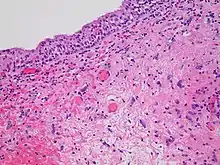

- Damage to the epithelial surfaces

- Epithelial surfaces may sustain damage from radiation therapy.[19] Depending on the area being treated, this may include the skin, oral mucosa, pharyngeal, bowel mucosa, and ureter. The rates of onset of damage and recovery from it depend upon the turnover rate of epithelial cells. Typically the skin starts to become pink and sore several weeks into treatment. The reaction may become more severe during the treatment and for up to about one week following the end of radiation therapy, and the skin may break down. Although this moist desquamation is uncomfortable, recovery is usually quick. Skin reactions tend to be worse in areas where there are natural folds in the skin, such as underneath the female breast, behind the ear, and in the groin.